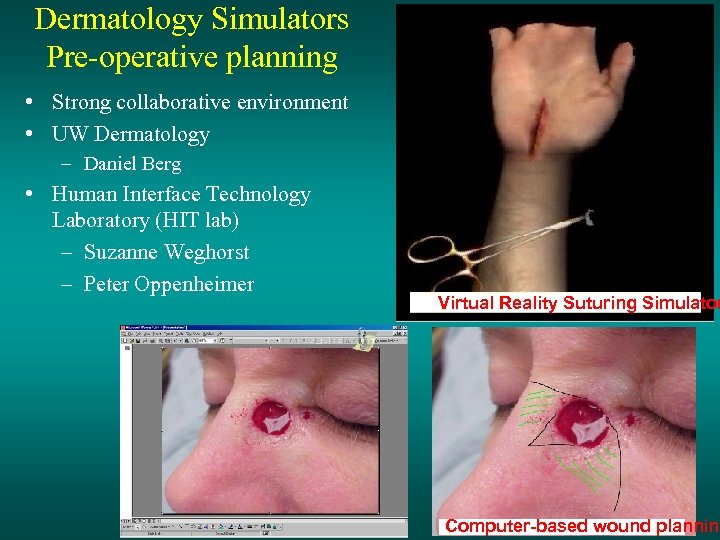

Dermatology Simulators Pre-operative planning • Strong collaborative environment • UW Dermatology – Daniel Berg • Human Interface Technology Laboratory (HIT lab) – Suzanne Weghorst – Peter Oppenheimer Virtual Reality Suturing Simulator Computer-based wound planning

Dermatology Simulators Pre-operative planning • Strong collaborative environment • UW Dermatology – Daniel Berg • Human Interface Technology Laboratory (HIT lab) – Suzanne Weghorst – Peter Oppenheimer Virtual Reality Suturing Simulator Computer-based wound planning